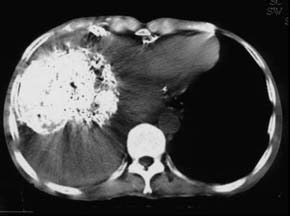

男友拖朋友到处打听治疗我病的方法,无意中得知南京太乙堂中医院在治疗肿瘤上口碑一直不错,于是带着我去接受治疗。专家给我做了详细检查之后跟我说目前对肾癌治疗根据我个人的具体情况如疾病情况、身体情况、包括经济情况,制定个科学、可行的治疗方案,决定采用“扶正祛邪·抗癌消瘤体系”进行治疗。